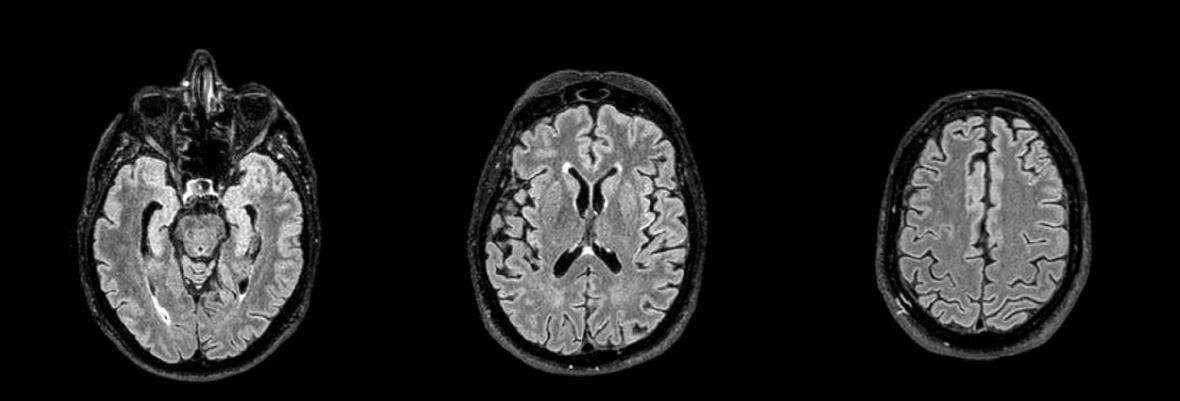

El segundo paciente femenino de 51 años tenía antecedente de esclerosis múltiple de más de 10 años de evolución en control evolutivo. Se analizaron las imágenes convencionales que mostraban estabilidad en la carga lesional sin evidencia de nuevas lesiones ni lesiones activas y signos de involución cerebral. En el reporte de Inteligencia artificial se mostró segmentación de lesiones en secuencia FLAIR, la cuantificación precisa del número de lesiones y su volumen total. También se cuantificó el grado de atrofia y se observó un volumen cerebral global por debajo del percentil 1 % para el grupo etario (Figuras 9 y 10).

Figura 7: Resonancia magnética de cerebro. Corte axial Flair

Parénquima cerebral sin particularidades. No se observan signos de leucopatía ni lesiones ocupantes de espacio.

Figura 9: Resonancia magnética de cerebro. Corte sagital flair.

Sagital FLAIR con segmentación de lesiones desmielinizantes